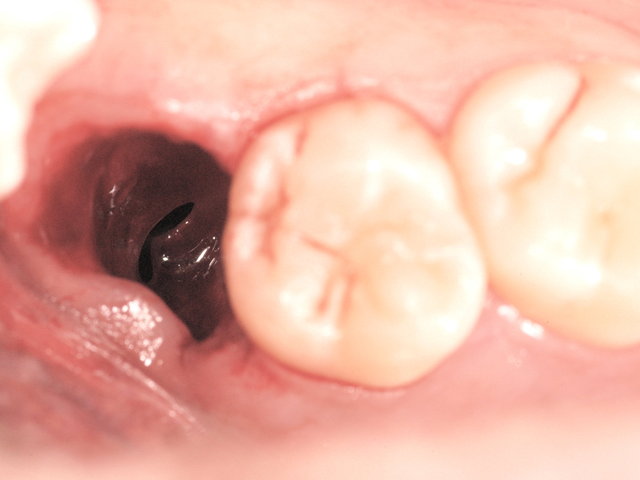

Tiefe Karies wegen eines benachbarten Weisheitszahnes

Sichtbarer Nerv im Zahnfach

Tiefe Karies wegen eines benachbarten Weisheitszahnes ...